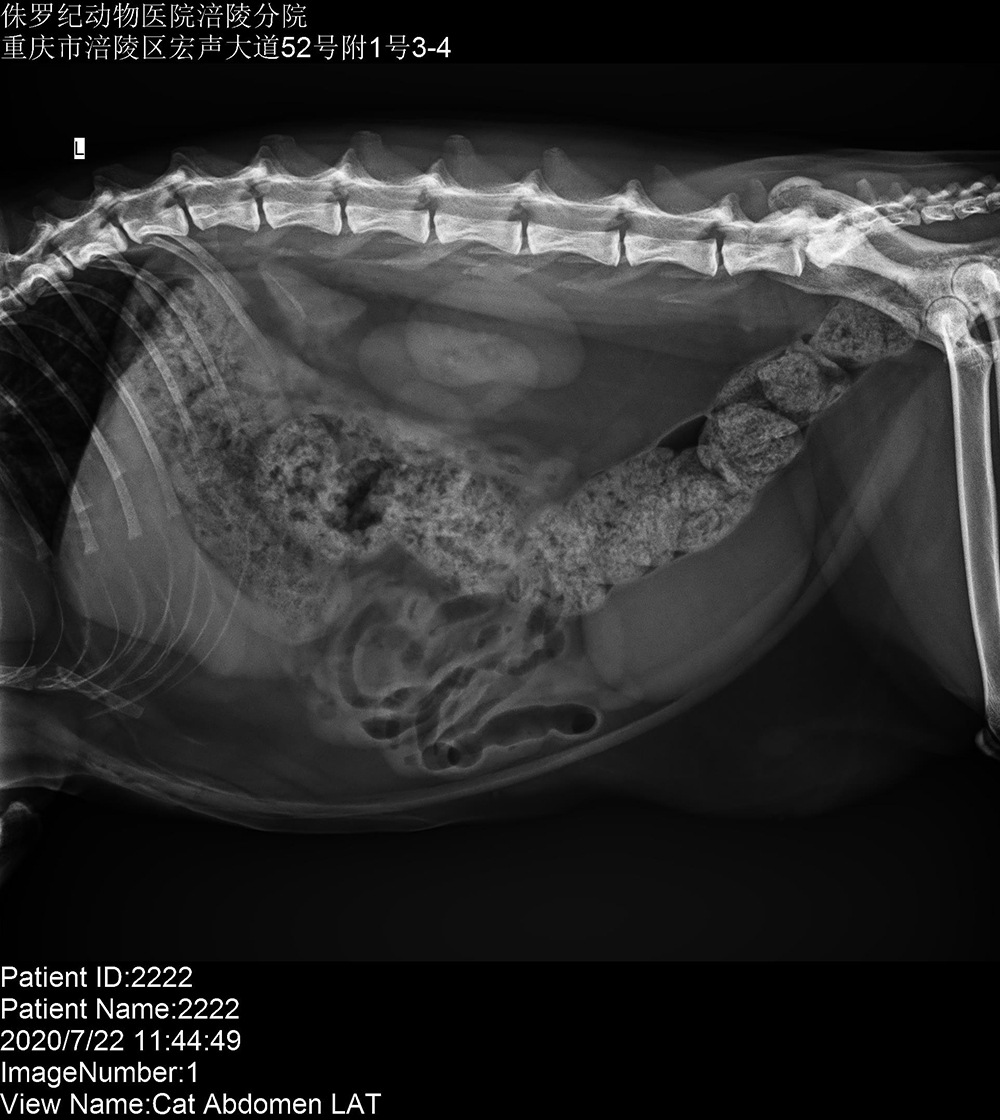

重慶侏羅紀動物(wù)醫(yī)院涪陵分(fēn)院 2020/7/23 上(shàng)一(yī)篇: 沒有(yǒu)了(le) 下(xià)一(yī)篇: 寵愛(ài)國(guó)際動物(wù)醫(yī)院重慶彈子(zǐ)石分(fēn)院